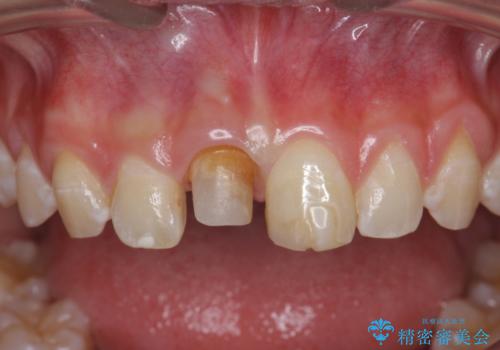

前歯をきれいにしたい ジルコニアクラウンによる審美治療

- 前歯の見た目の改善を求めて来院されました。

ジルコニアクラウンによる審美性の改善を計画します。

失活歯のため捻転を改善し、根管治療は特に希望されなかったのでそのままとしました。

今回失活歯であったため捻転を取り反対側の前歯に揃えて補綴を行うことができました。